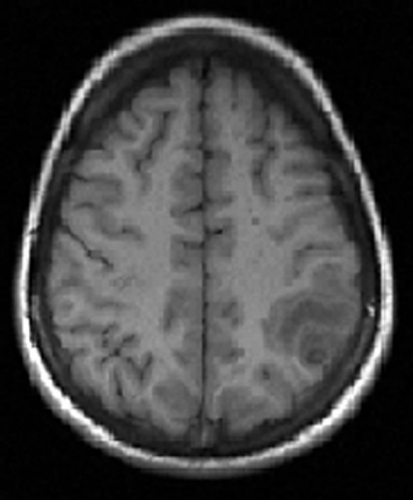

Datortomografi (DT) och magnetresonanstomografi (MRT) påvisade en solitär, drygt 1 cm stor rundad lesion i övergången mellan vit substans och kortex parietalt i vänster hjärnhalva. Förändringen var omgiven av en kontrastuppladdande kapsel och av ett ödem, som sträckte sig över hela den främre delen av vänster hemisfär (Figur 1 och Figur 2).

Differentialdiagnosen ur neuroradiologisk synvinkel omfattade bakteriell hjärnabscess och parasitinfektion, främst neurocysticerkos, men neoplasi (hjärntumör eller tumörmetastas) kunde inte med säkerhet uteslutas. Bilderna förmedlades via patientens familj till flera neurokirurger i patientens hemland, som samstämmigt ansåg att neurocysticerkos var mest sannolikt. I cerebrospinalvätska var antalet av polynukleära leukocyter diskret förhöjt (2,5 106/l). Western blot-analys av serum och cerebrospinalvätska påvisade inga antikroppar mot Taenia solium. Serologi för Toxoplasma gondii var negativ. I fecesdirektmikroskopi och i tejpprov fann man inga maskägg. Normalt ögonfynd konstaterades vid ögonläkarundersökning. Ett elektroencefalogram visade diffus förlångsamning med vänstersidig övervikt.

Nästa steg är en DT- eller hellre en MRT-undersökning av hjärnan. Fynden i DT kan vara relativt ospecifika medan MRT ger bättre information om cystans innehåll. Vid neurocysticerkos ser man en eller flera cystor med kontrastladdande rand. Ibland kan parasitens skolex identifieras som en millimeterstor punkt, vilket gäller som ett säkert diagnostiskt tecken [6]. Äldre cystor förkalkas. Om den radiologiska undersökningen visar en patologi förenlig med neurocysticerkos analyseras serum eller cerebrospinalvätska med antikroppstest (immunblot-teknik enligt Tsang [7]). I Sverige utförs testet inte rutinmässigt, men prov kan lämnas till Smittskyddsinstitutet, som vidarebefordrar det till Schweiz. Testets specificitet anges till 100 procent, medan sensitiviteten varierar: upp till 95 procent vid multipla, icke-förkalkade intracerebrala lesioner och enbart ca 50–80 procent vid solitära cystor. Testet kan inte skilja mellan aktuell och genomgången infektion. Eosinofili i cerebrospinalvätska (men inte i blod) kan tyda på neurocysticerkos; differentialräkning av celler i cerebrospinalvätska kan genomföras manuellt i ett färskt likvorprov.

Anamnesen och den radiologiska bilden gjorde att den kliniska misstanken om neurocysticerkos var relativt stark. Däremot var de radiologiska förändringarna inte entydiga, någon skolex kunde inte identifieras. Dessutom var serologin negativ, och i likvor fanns en lätt pleocytos.